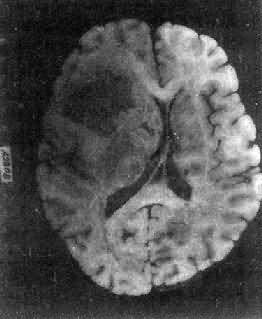

一、中枢神经肿瘤(一)胶质瘤 胶质瘤(glioma)具有特异的不同于其它部位肿瘤的生物学特性: (1)良恶性的相对性:无论高度分化或低度分化的胶质瘤均呈浸润性生长,更无包膜形成。生长迅速、间变程度高的肿瘤,与周围组织截然不同,故边界往往较清楚。 第三脑室分化良好的幼年型星形胶质细胞瘤,由于位于手术禁区,无法进行切除。因此预后不佳。 (2)局部浸润:胶质瘤的浸润性生长主要累及血管周围间隙、软脑膜、室管膜、神经纤维束间。 (3)转移:①脑脊液转移是颅内肿瘤常见的转移方式,相当于颅外恶性肿瘤细胞的淋巴道浸润和转移,特别是位于脑室旁、脑池旁的肿瘤发生这种转移的机会更多。②颅外转移极少见,其中80%以上均有颅脑外科手术史。 1.星形胶质细胞瘤(astrocytoma) 本瘤约占颅内肿瘤的30%,占神经胶质瘤的70%以上。男性较多见。最近研究表明该肿瘤中原癌基因sis有过度表达,erb-B1则有放大。 肉眼观,肿瘤为数厘米的结节至巨大块状。分化较好的肿瘤,境界不清;而分化程度较低的肿瘤则境界分明。瘤体灰白色。质地视肿瘤内胶质纤维多少而异,或硬、或软、或呈胶冻状外观,并可形成大小不等的囊腔。由于肿瘤的生长、占位和邻近脑细胞的肿胀,脑的原有结构因受挤压而扭曲变形(图16-23)。

图16-23 星形胶质细胞瘤 左大脑半球肿胀,肿瘤边界不清,部分呈胶冻状 镜下,肿瘤细胞形态多样,可相似于纤维型星形胶质细胞、原浆型星形胶质细胞和肥胖星形胶质细胞,故分别称为纤维型、原浆型和肥胖型星形胶质细胞瘤。前二者为良性肿瘤,后者性质介于良恶性之间。如肿瘤细胞出现间变,细胞密度增大,异型性明显,核深染,出现核分裂像,毛细血管内皮细胞增生,则为间变性星形胶质细胞瘤,为恶性肿瘤。 高度恶性的星形胶质细胞瘤称为多形性胶质母细胞瘤(glioblastoma multiforme),多见于成人。肿瘤好发于额叶、颞叶白质,浸润范围广,常可穿过胼胝体到对侧,呈蝴蝶状生长(图16-24)。瘤体因常有出血坏死而呈红褐色。镜下,细胞密集,异型性明显,可见怪异的单核或多核瘤巨细胞。出血坏死明显,是其区别于间变性星形胶质细胞瘤的特征。毛细血管明显增生,内皮细胞增生、肿大,可导致管腔闭塞和血栓形成。肿瘤发展迅速,预后极差,患者多在2年内死亡。